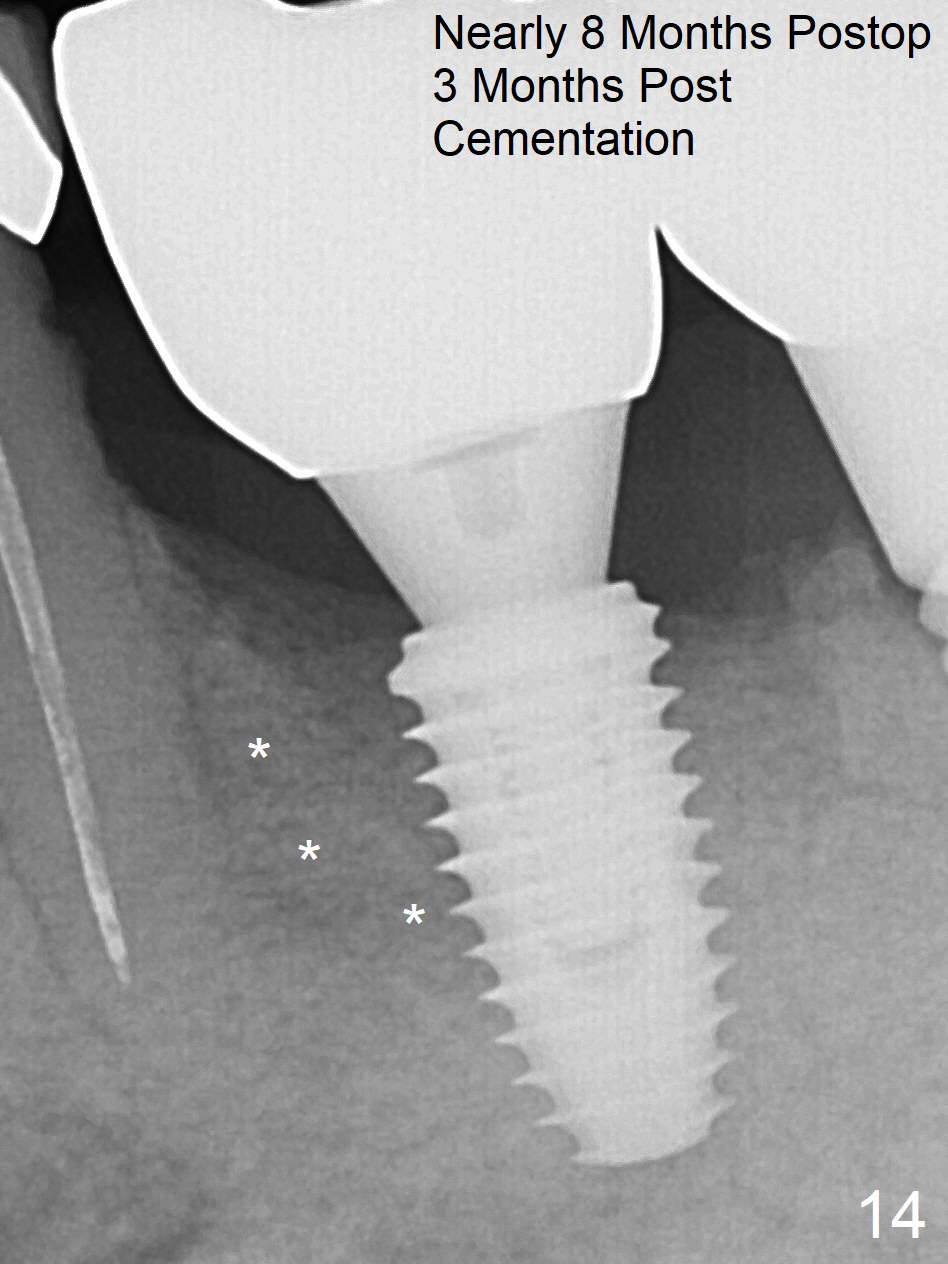

Extraction of the residual roots at #19 (Fig.1) is difficult, partially due to the hard one. The latter contributes to primary stability of 5x10 mm IS implant placed in the septum (Fig.2 (*),3). After change of cementation abutment (5.2x4.5(2) mm (short for provisional)) to hexed temporary abutment (5.2x8(2) mm), Collagen plug and Vera Graft are placed in the remaining mesial and distal socket (Fig.4 *). The last PA is taken when the temporary abutment (Fig.6 (<: hexed portion)) and provisional (P) are removed for modification. Before the abutment/provisional complex returns, a 2nd round of graft is placed (Fig.5 *). After the complex is seated, a 3rd round of graft is placed buccally (Fig.7). The temporary abutment is retightened 2 months postop (Fig.8). The implant appears to be osteointegrated 3.5 months postop (Fig.9). The gingiva looks healthy with (Fig.10) and without the provisional (Fig.11,12). It appears that there is no or minimal buccal plate loss. After insertion of a 5.7 x3 mm 15 degree (B-type) angled abutment (Fig.13) and height adjustment, impression is taken. The provisional is reseated after impression. The mesial bony defect seems to have been repaired nearly 8 months postop, 3 months post cementation (Fig.14 *). The bone density increases mesially 11 months post cementation (Fig.15).